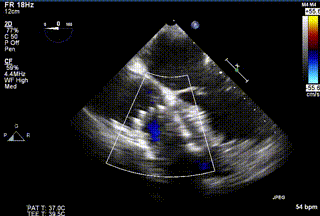

2021年12月24日,復(fù)旦大學(xué)附屬中山醫(yī)院葛均波院士團(tuán)隊(duì)成功應(yīng)用LuX-Valve Plus為一例極重度三尖瓣反流(TR)合并房顫、房缺的患者完成了經(jīng)血管三尖瓣置換術(shù),這是在前基礎(chǔ)上,本周完成的第三例經(jīng)血管三尖瓣置換手術(shù),葛均波院士、周達(dá)新教授等與心外科魏來教授、賴顥教授,心超室的潘翠珍教授、李偉教授及麻醉科的郭克芳教授共同完成了本周手術(shù),均獲得圓滿成功!患者術(shù)后超聲顯示無TR,臨床癥狀明顯改善。本周手術(shù)的成功也為L(zhǎng)uX-Valve Plus救治性臨床研究添上了濃墨重彩的一筆。

三例患者入院后,葛均波院士團(tuán)隊(duì)周達(dá)新教授、潘文志教授、張?jiān)床┦俊㈥惿┦考靶某业呐舜湔浣淌?、李偉教?/strong>對(duì)患者的情況進(jìn)行詳細(xì)評(píng)估和討論,最終決定為三例患者選擇LuX-Valve Plus40mm、50mm和50mm型號(hào)的瓣膜進(jìn)行手術(shù)治療。手術(shù)后即刻拔除氣管插管,術(shù)后患者三尖瓣反流癥狀得到顯著改善,復(fù)查心超結(jié)果顯示人工三尖瓣瓣膜支架固定穩(wěn)定,瓣葉關(guān)閉形態(tài)未見異常,未見明顯反流。